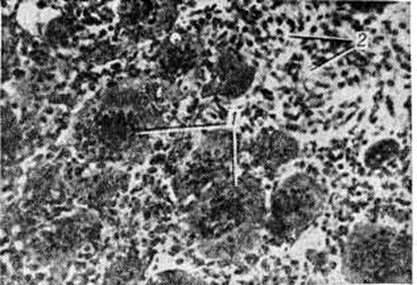

ОстеобластокластомаОстеобластокластома (греческий osteon кость + blastos росток + klastos разбитый + -oma; синонимы: гигантоклеточная опухоль кости, гигантома, остеокластома) — солитарная остеогенная опухоль, характеризующаяся наличием гигантских многоядерных клеток типа остеокластов. Чаще Остеобластокластома носит доброкачественный характер, но существует и злокачественный её вариант. Термин предложен А. В. Русаковым и принят в СССР, хотя в других странах большее распространение получил термин «гигантоклеточная опухоль». Термины «миелогенная гигантоклеточная опухоль», «опухоль из миелоплаксов», «бурая опухоль» устарели и не применяются. В классификации опухолей костей ВОЗ остеобластокластома обозначена под названием «гигантоклеточная опухоль» и отнесена к новообразованиям неясного гистогенеза. Остеобластокластома составляет около 4% всех опухолей костей, сравнительно редко встречается в возрасте до 20 и свыше 55 лет, примерно 75% Остеобластокластома наблюдается в возрасте 30—40 лет, несколько чаще у женщин. По мнению большинства исследователей Остеобластокластома не встречается в возрасте до 15 лет. Излюбленная локализация — эпиметафизы длинных трубчатых костей. Ряд учёных считает, что Остеобластокластома возникает в эпифизе и затем распространяется на прилежащий метафиз, другие придерживаются мнения о первичном поражении метафиза. Остеобластокластома может локализоваться в различных отделах скелета, но редко поражает позвоночник, кости черепа, а также мелкие кости кистей и стоп. В редких случаях Остеобластокластома имеет внекостную локализацию. По мнению многих исследователей, в этиологии Остеобластокластома важную роль играет травма — у многих больных с Остеобластокластома в анамнезе часто имеются указания на однократную или повторную травму области опухолевого поражения. Патологическая анатомия. Макроскопически опухоль имеет пёстрый вид — на разрезе красно-серые участки чередуются с бурыми очагами гемосидероза, желтоватыми участками некроза, белесоватыми зонами фиброза и кистозными полостями, содержащими серозную или кровянистую жидкость. Наряду с преобладающими мягкими массами встречаются более плотные участки фиброза и оссификации. Костные перегородки в толще опухоли не обнаруживаются, однако преимущественно в периферических отделах могут наблюдаться явления костеобразования в виде остеоидных или обызвествленных костных пластинок. Опухоль деформирует кость в области эпиметафиза за счёт распространения под корковое вещество, причём оно в этих участках резорбируется, а со стороны надкостницы образуется новая костная «скорлупа». Иногда истончённое корковое вещество повреждается и опухоль распространяется на прилежащие к поражённой кости мягкие ткани. В редких случаях опухоль распространяется в близлежащие сустав или кость. В области Остеобластокластома может наступить патологический перелом кости, в результате которого макроскопическая картина становится ещё более пёстрой за счёт кровоизлияний, некроза, репаративных процессов и другие Микроскопически Остеобластокластома построена из клеточных элементов двух типов: преобладают слегка вытянутые мелкие клетки с округлым или овальным ядром, среди которых более или менее равномерно распределены многоядерные гигантские клетки, содержащие иногда до 50—100 ядер (рисунок 1), практически не отличающихся от ядер мелких клеток. В одноядерных клетках встречаются митозы, в многоядерных — фигуры деления отсутствуют. Наряду с этими двумя видами клеток в Остеобластокластома встречаются фибробласты, поля ксантомных клеток, участки кровоизлияний с макрофагальной реакцией. В центральных отделах Остеобластокластома отмечается своеобразный бессосудистый тканевой кровоток — кровь циркулирует непосредственно между клетками, образуя местами небольшие скопления, как бы «заболачивая», по выражению А. В. Русакова, ткань опухоли и приводя к образованию кист. Это даёт основание некоторым исследователям говорить о возможности исхода Остеобластокластома в костную кисту (смотри полный свод знаний). Значительное число кровеносных сосудов выявляется преимущественно по периферии новообразования. При интенсивном росте опухоли многоядерные гигантские клетки утрачивают чёткость контуров, число ядер в них увеличивается. При медленном росте многоядерные гигантские клетки уменьшены в размерах, округлой формы с чёткими контурами, содержат небольшое количество ядер. В ряде случаев на первый план выступают явления фиброза. При этом многоядерные клетки ещё больше уменьшаются в размерах, имеют неровные зазубренные очертания, содержат значительно меньше ядер, цитоплазма их становится плотной, базофильной. При исходе Остеобластокластома в кисту опухолевая ткань иногда почти полностью редуцируется. |

Рис. 1. | ||